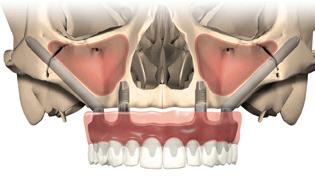

Antipov DDS - 8

Children's Choice Dental Care - 52

Citrus Heights Dental - 41

Eureka Dental - 41

Fine Touch Dental - 11

Global Smiles - 96

Kravchuk DDS - 32

NOVA Dental - 4

Rocklin Plaza Dental - 24